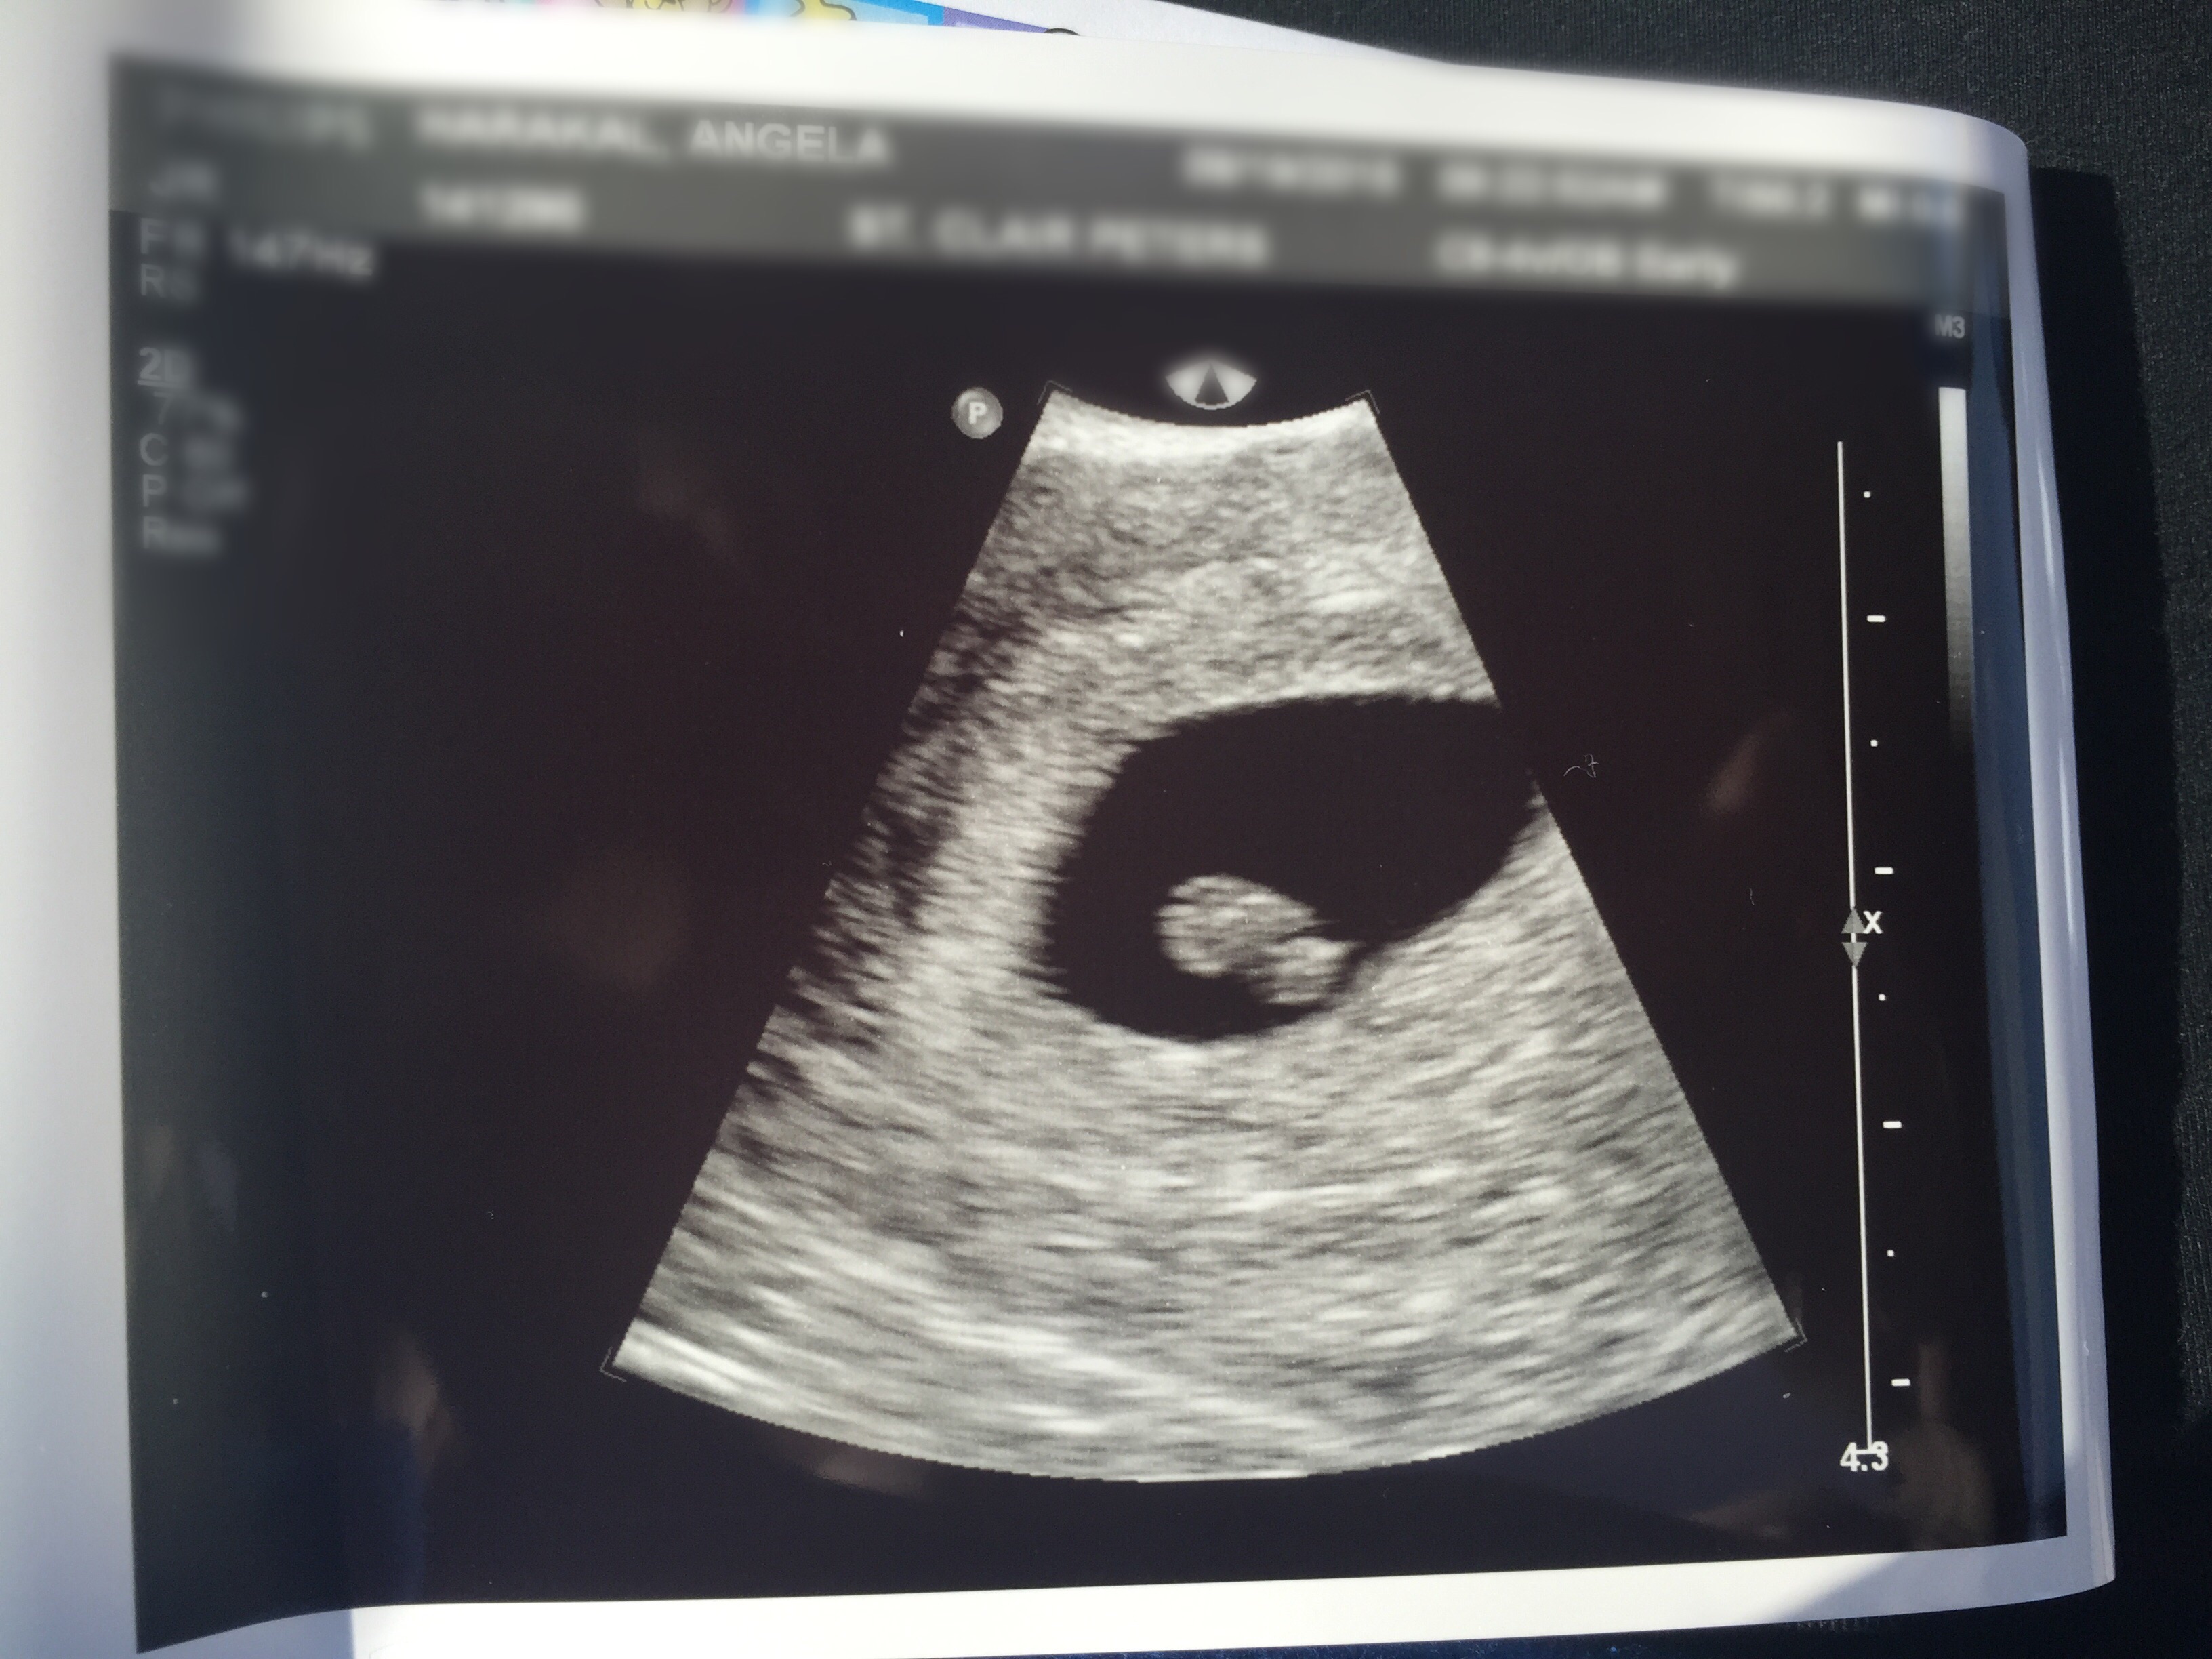

I am expecting twins. At 6w6day pregnant I had my u/s on 8/13 ( baby a measure at seven weeks and baby b 6w5days. Both of them doing great with strong hearts beats. So happy and exciting for all of us.